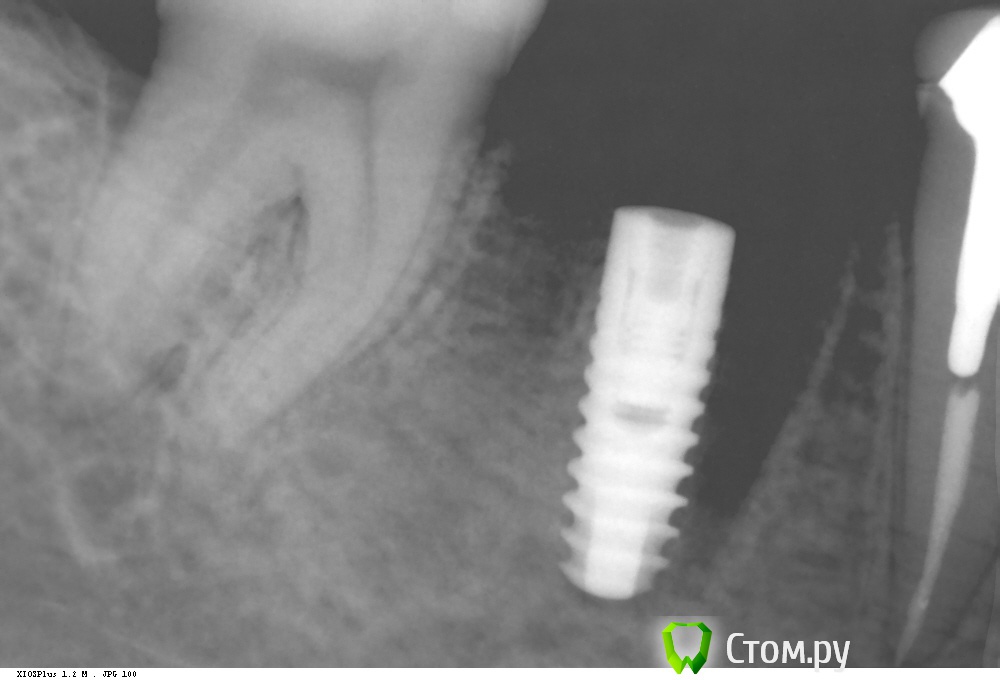

Dr.Sham Опубликовано 8 октября, 2014 Поделиться Опубликовано 8 октября, 2014 Удаление в другой клинике. КТ. Установка имплантата. кость была мягкая, но была со всех сторон по 2 мм минимум. Рентген оч жесткий. Через 2 месяца раскрытие имплантата, имплантат был окружен костью, как обычно, пришлось его раскапывать. ФДМ. Заживление без особенностей. Сегодня была фиксация коронки, сделал рентген для проверки фита. И...потерял дар речи. Десны маловато, но вокруг все кератинизировано. ФДМ узкий был. C чем может быть связана резорбция? Ссылка на комментарий

Dr.Sham Опубликовано 8 октября, 2014 Автор Поделиться Опубликовано 8 октября, 2014 (изменено) Спрогнозировать потерю костной ткани по вертикали после удаления довольно сложно. Поэтому ждать нужно было немного больше или ставить глубже.Спасибо за ответ. Вопрос тогда, сколько ждать? и рентген не показывает истинную картину. на рентгене в позиции медиального канала как будто пустота, а интраоперационно там была молодая костная ткань, так же, как и сверху.Какая тактика дальнейшая? По срокам, если честно, это стандартно для меня - 2 месяца, как здесь, например. Третий раз редактирую между вторым и третим рентгеном - 1 месяц на фдмке. рентген - не оч информативен, повторюсь, имплантат "раскапывал", поэтому и вопрос, что могло пойти не так... Изменено 8 октября, 2014 пользователем Dr.Sham Ссылка на комментарий